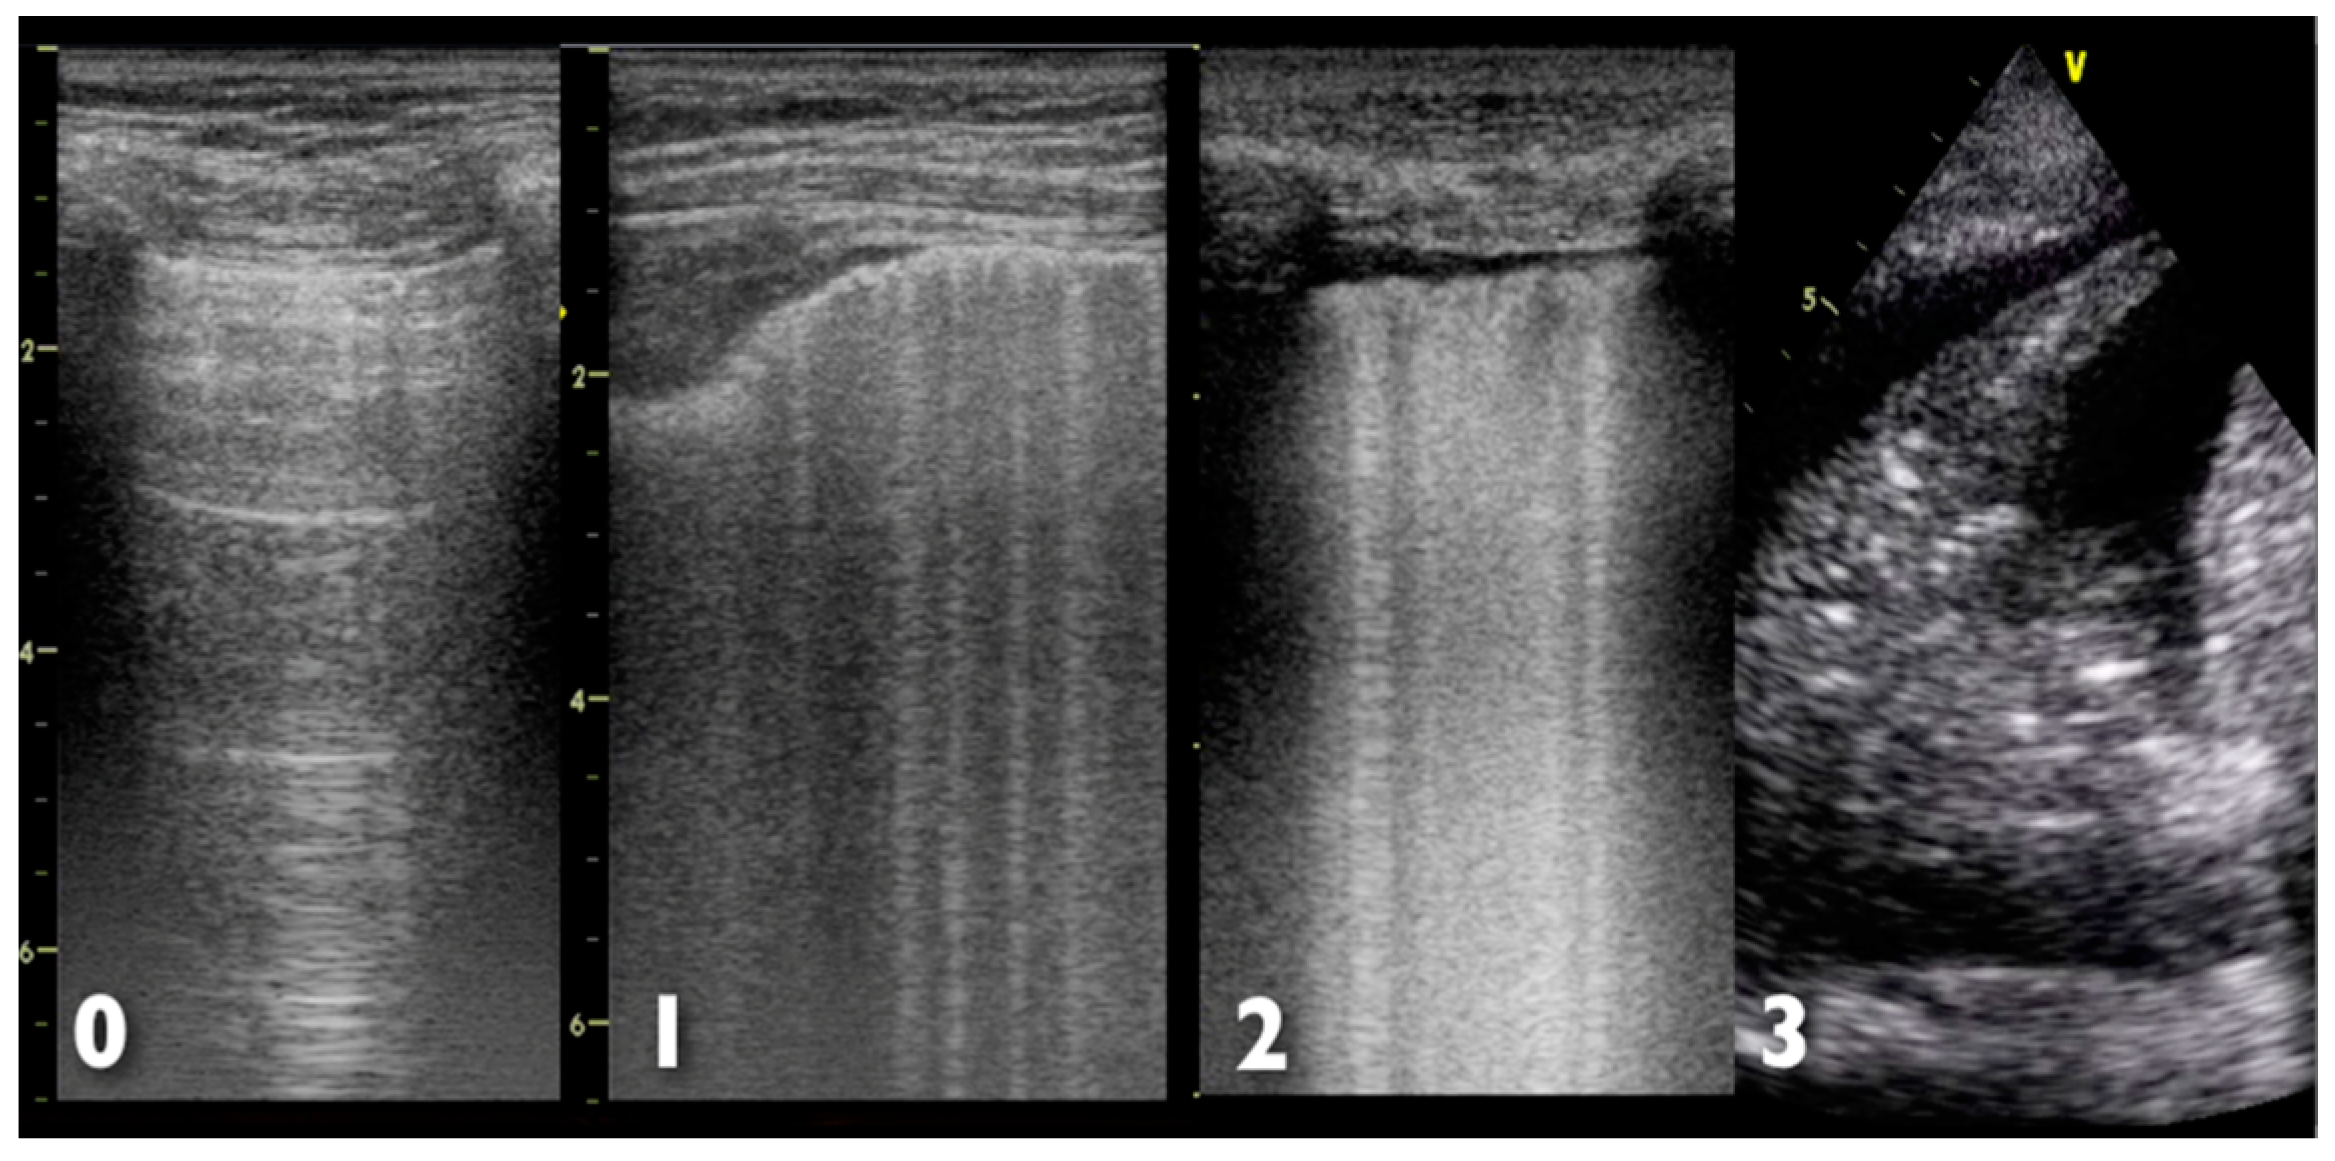

Further help in diagnosis and management of ARDS may come from the study of ultrasonographic artefacts produced by air, lung parenchyma, chest wall and pleura [35,36]; the pivotal finding in patients with respiratory failure is a B-line artifact, defined as the presence of a discrete vertical hyperechoic reverberation artefact that arises from the pleural line [36]. The finding of three or more B-lines in one intercostal space is considered abnormal and is referred to as a B-pattern [36]. The interstitial involvement of the lungs correlates with the presence of B-lines, and a preponderance of B-pattern is suggestive of an alveolar process, rather than a non-alveolar cause [37]. However, the presence of a bilateral B-pattern does not permit a differentiation between ARDS and cardiogenic pulmonary oedema [38]. Indeed, in ARDS, more commonly than in cardiogenic pulmonary oedema, a non-homogeneous distribution of B-pattern, C (consolidative) pattern and pleural line abnormalities are observed [39]. The systematic use of thoracic ultrasonography as a tool for bedside evaluation of ARDS evolution has been suggested by some authors [40,41]. Figure 4 shows the different ultrasonographic finding of lung examination; ultrasonographic findings in cardiogenic pulmonary oedema and ARDS are summarized in Table 3.

Figure 4.

Possible ultrasonographic findings at lung examination. 0: Normal aeration with normal sliding, with A-lines pattern; 1: Multiple B-lines but separated by at least 5 mm; 2: Multiple, coalescent, not well-separated B-lines; 3: Lung consolidation, hyperechoic area with air bronchogram. Numbers on the left side of each ultrasound image represent the depth (in cm).